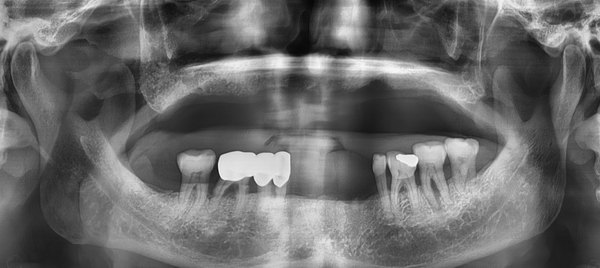

이렇게 치아가 없던 분도 아래 쪽 앞니와 어금니는 네비게이션 임플란트 하시고

위는 틀니로 윗 입술도 빵빵해지면서 안정적인 치아와 입주변의 모습이 완성되셨습니다.